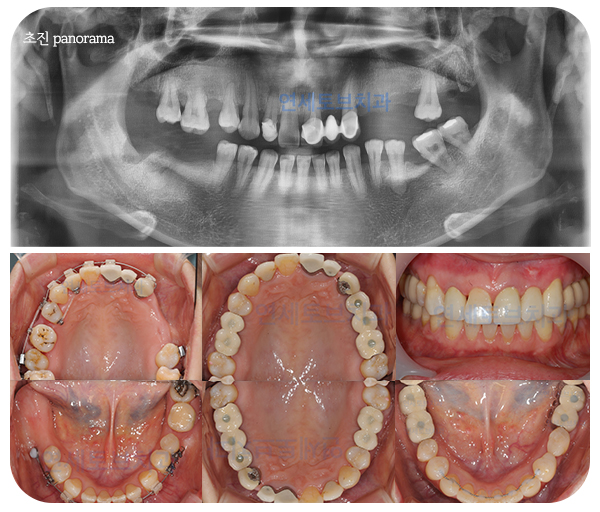

충치 진행 과정

법랑질의 표면 충치 시작

상아질까지 충치 진행

치아 신경 조직 손상

치아 뿌리까지 손상

법랑질은 치아 위쪽, 구강에

노출되는 부분입니다.

충치가 상아질까지 들어가게 되면,

그 진행 범위가 넓습니다.

치아의 표면뿐만 아니라

안쪽까지 까맣게 보입니다.

충치를 방치할 경우 치아 뿌리와

뿌리 주변까지 농이 생깁니다.